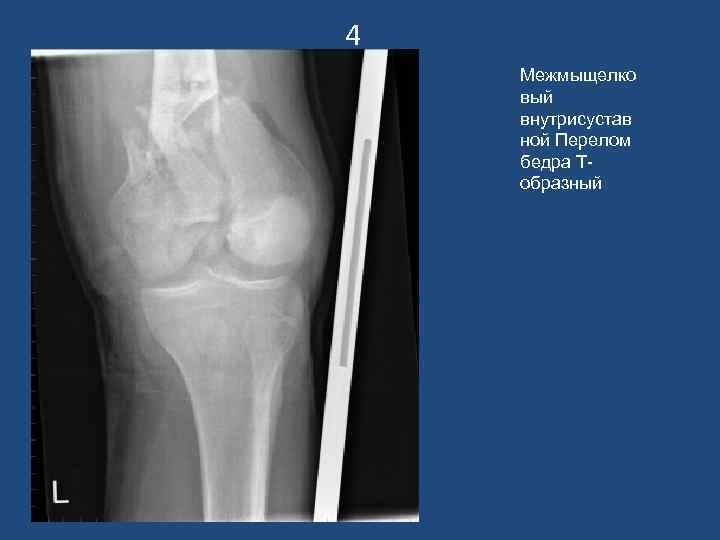

4 Межмыщелко вый внутрисустав ной Перелом бедра Тобразный